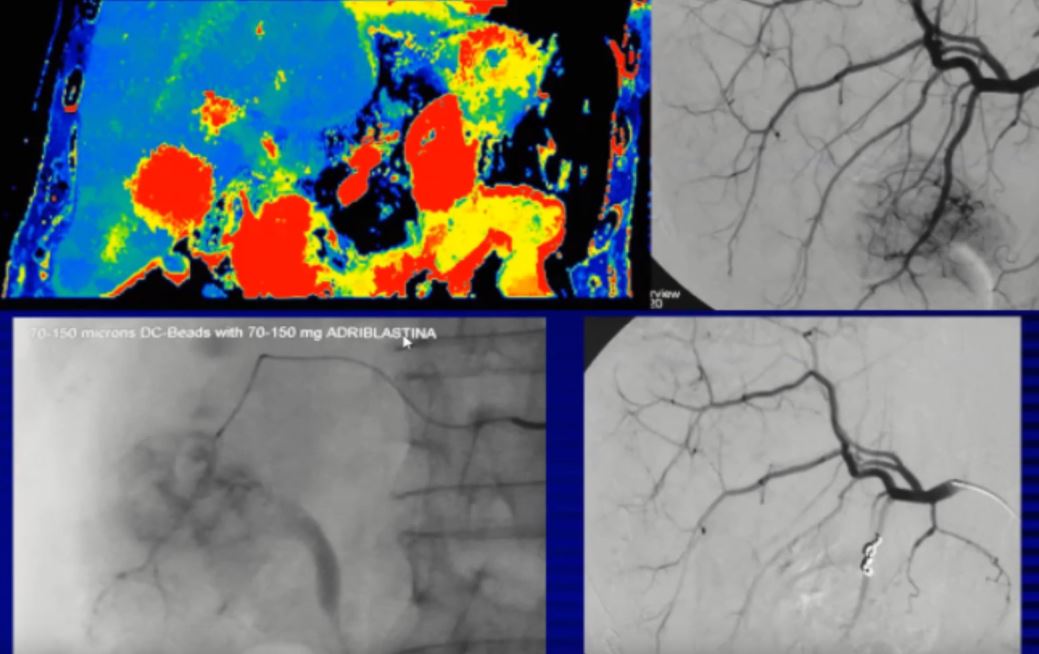

Παρουσίαση από τον Καθηγητή Ακτινολογίας ΑΠΘ Αδάμ Χατζηδάκη σχετικά με θεραπεία καρκίνου ήπατος με μέθοδο επεμβατικής ακτινολογίας χωρίς χειρουργείο.